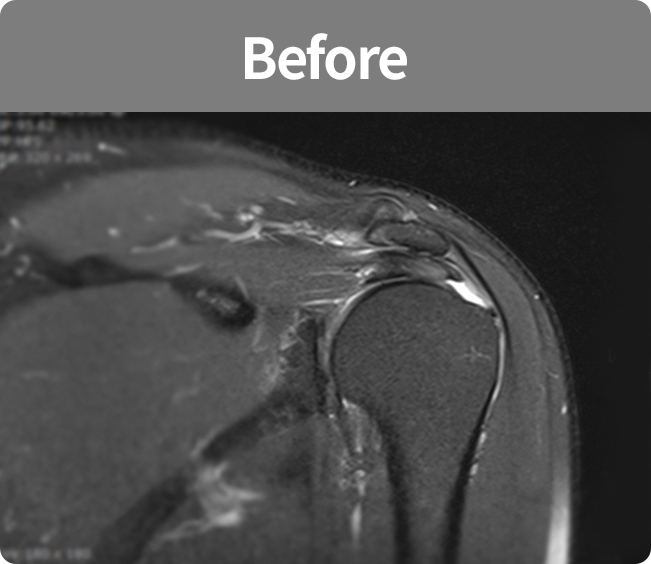

회전근개 봉합술

어깨뼈와 회전근개 힘줄이 충돌로 인하여 나타나는 염증 등을 관절경을 이용하여

견봉 부위의 염증 부위를 치료하고 견봉 부위의 마모로 인하여 거칠어진 부분을 넓게 확보해주는 수술법